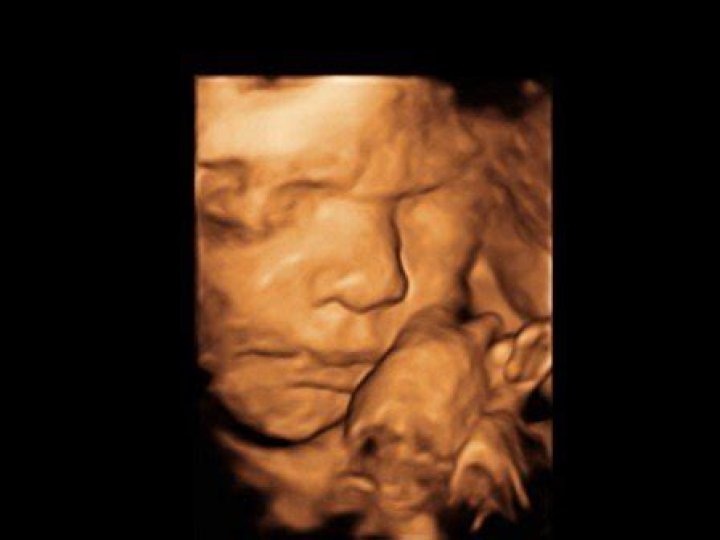

What does trisomy 18 look like on ultrasound?

Can you see trisomy on an ultrasound?

Trisomy 18, also known as Edwards’ syndrome, is a genetic disorder that affects babies and can often be diagnosed before birth. A fetal ultrasound during pregnancy can show features that are suggestive of trisomy 18, and the detection rate is about 90% during pregnancy weeks 14-21.